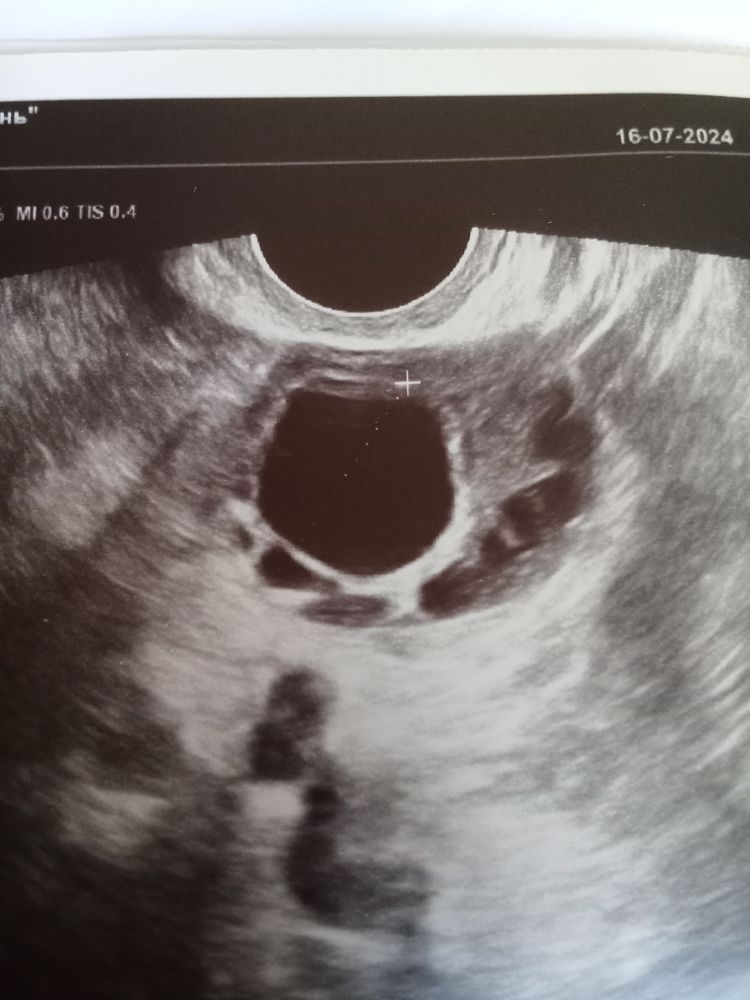

МалинКа, напишите что вам сказали. Так не люблю эту неопределенность, в прошлом цикле бхб, этот решила посмотреть на УЗИ чего там, а там узистка не уверена толком. Оранжевый поймал всплеск, через два дня вот такое УЗИ Изображение

Лидия, могу посоветовать Орликовскую, узист 👍🏼 принимает в доктор Арбитайло. Всегда во всем уверена. Ещё не подводила. А по фото я вообще подумала, что это функциональная киста 🤔 уж больно похожа

Лидия, это когда ДФ не лопается, он перерастает в кисту, то есть овуляция не происходит

Гром, а размер маленький 21.3 начались симптомы 2 фазы, ТТ 37.3, грудь болит, вот гад, подвёл меня. Но наверное лучше сходить ещё на УЗИ.

Лидия, у меня киста была 24мм. Попробуйте снова сходить. ЖТ все равно остаётся до самых М. Если О была, увидят.